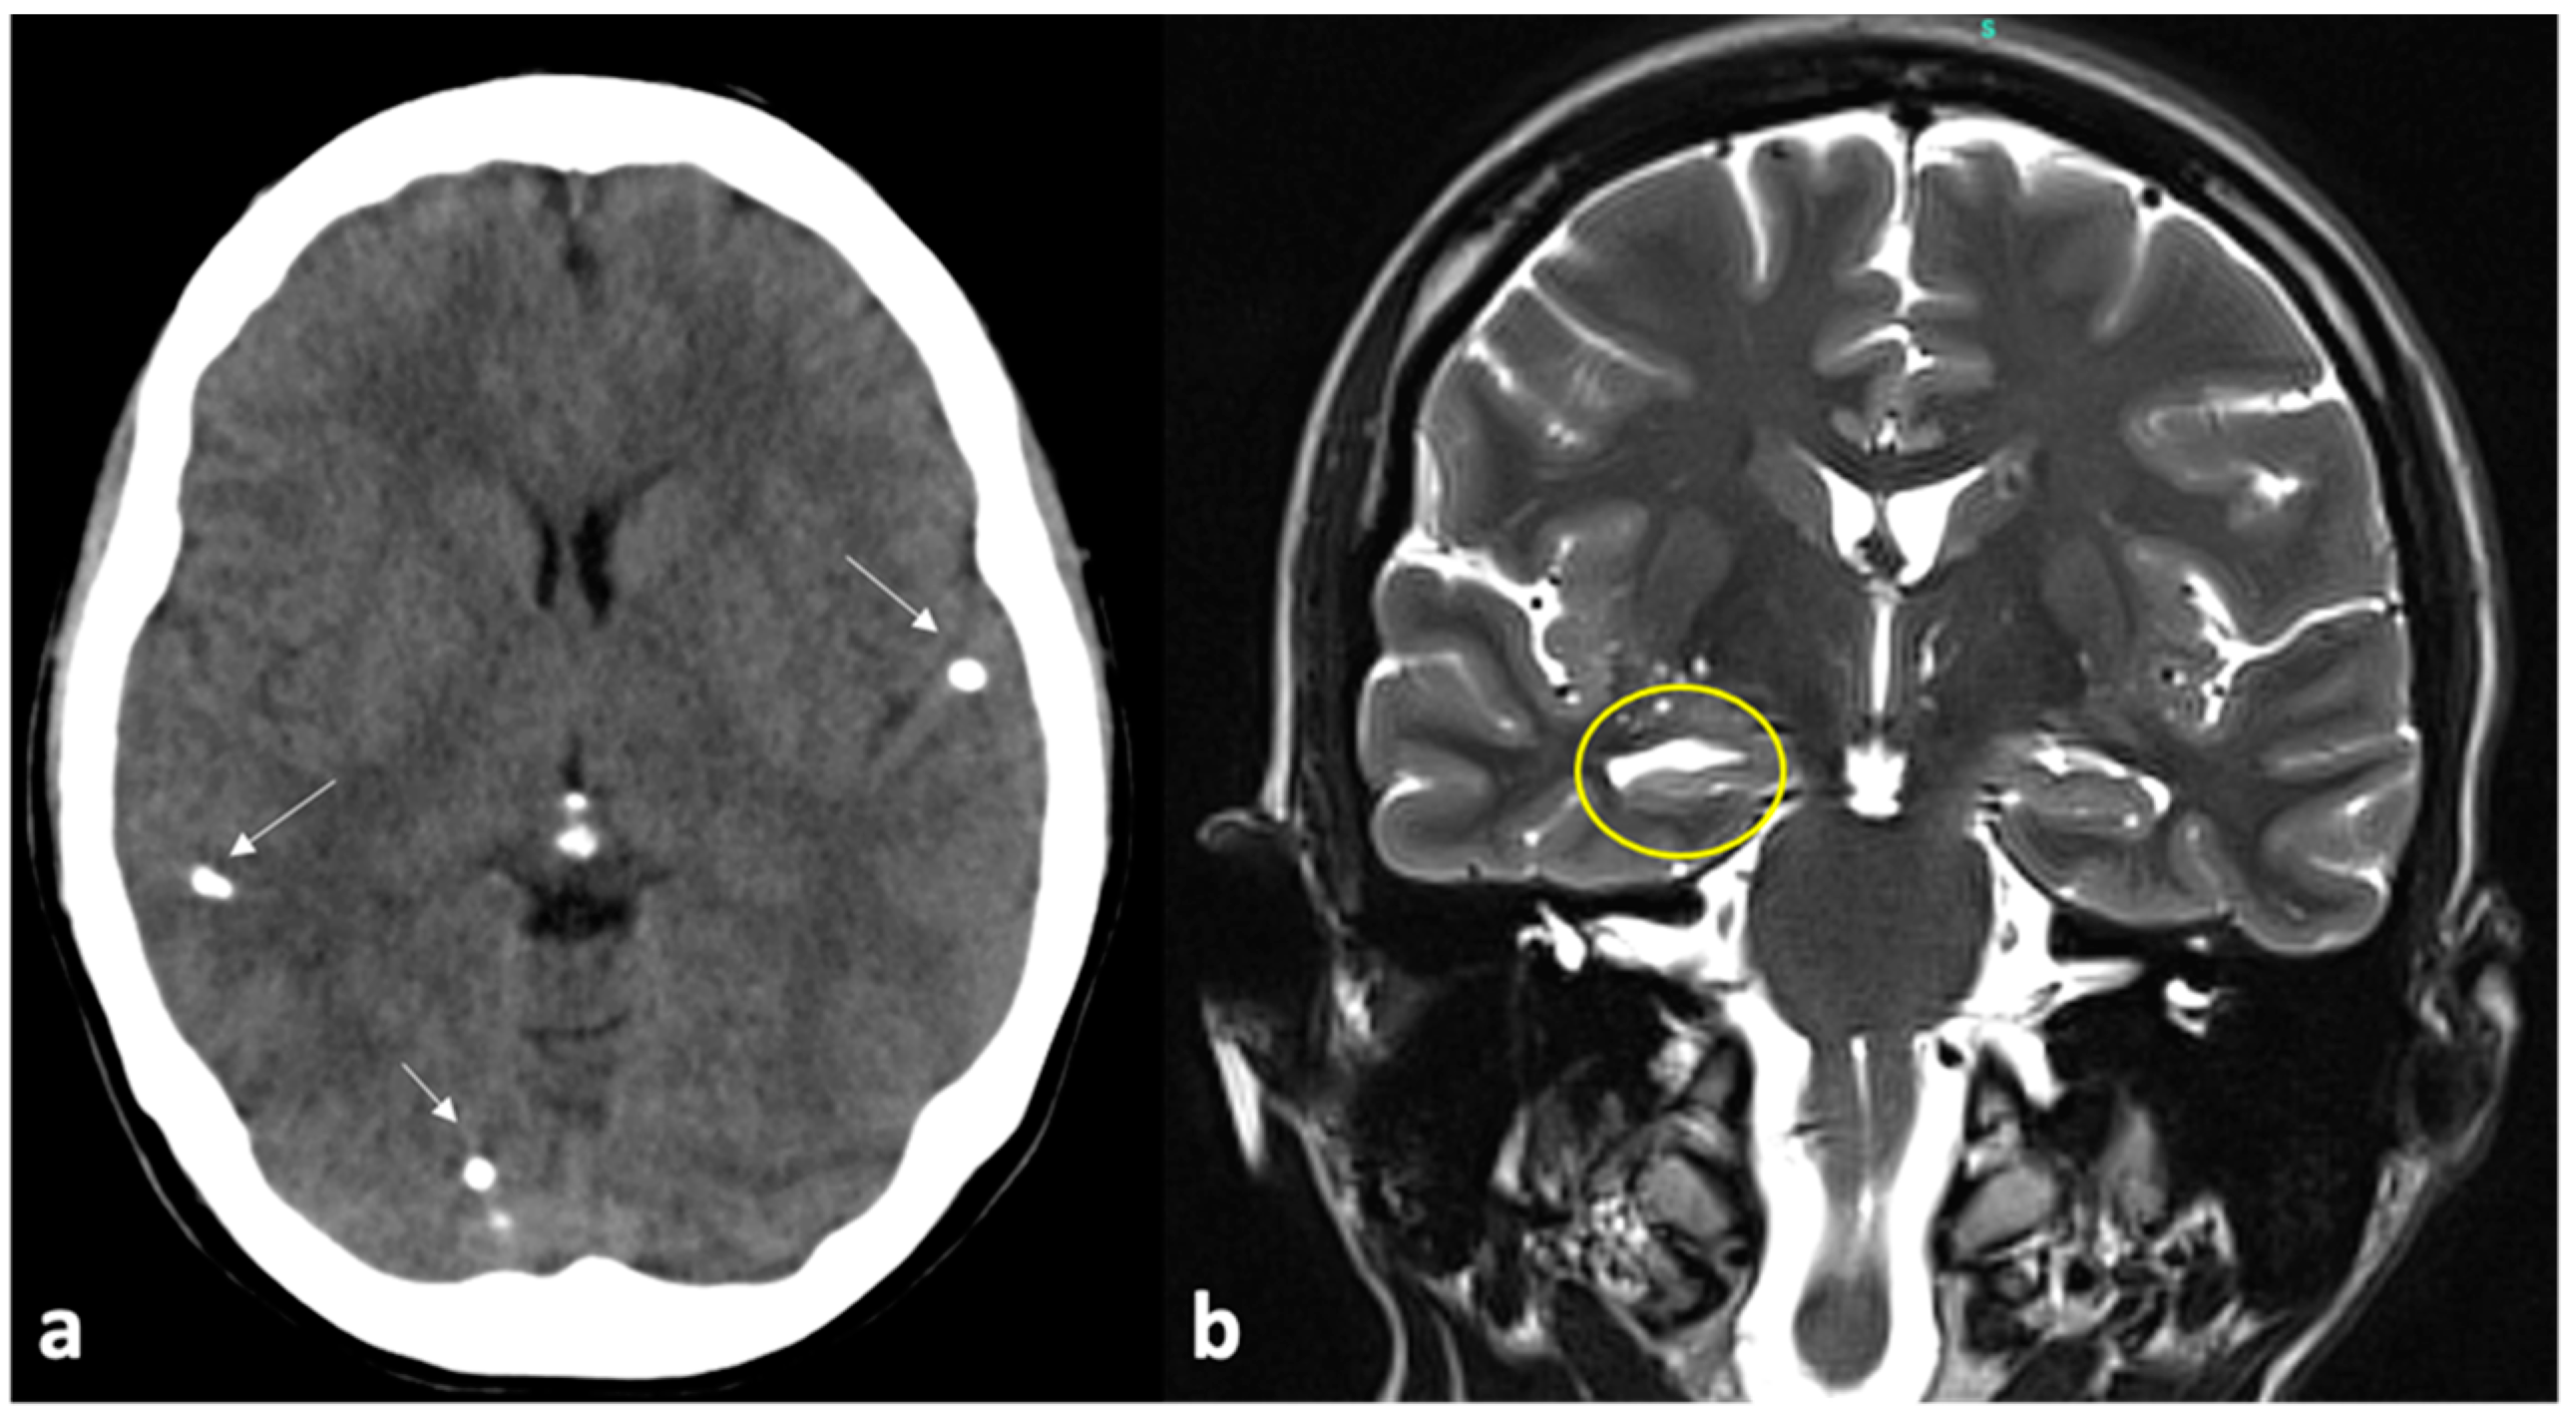

- Nash, T.E.; Del Brutto, O.H.; Butman, J.A.; Corona, T.; Delgado-Escueta, A.; Duron, R.M.; Evans, C.A.; Gilman, R.H.; Gonzalez, A.E.; Loeb, J.A.; et al. Calcific Neurocysticercosis and Epileptogenesis. Neurology 2004, 62, 1934–1938. [Google Scholar] [CrossRef] [PubMed]

- Herrick, J.A.; Maharathi, B.; Kim, J.S.; Abundis, G.G.; Garg, A.; Gonzales, I.; Saavedra, H.; Bustos, J.A.; Garcia, H.H.; Loeb, J.A.; et al. Inflammation Is a Key Risk Factor for Persistent Seizures in Neurocysticercosis. Ann. Clin. Transl. Neurol. 2018, 5, 630–639. [Google Scholar] [CrossRef] [PubMed]

- Nash, T. Edema Surrounding Calcified Intracranial Cysticerci: Clinical Manifestations, Natural History, and Treatment. Pathog. Glob. Health 2012, 106, 275–279. [Google Scholar] [CrossRef] [PubMed]

- Coyle, C.M. New Insights into Calcified Neurocysticercosis: Closing the Knowledge Gap. Clin. Infect. Dis. 2021, 73, e2601–e2603. [Google Scholar] [CrossRef]

- Rathore, C.; Thomas, B.; Kesavadas, C.; Abraham, M.; Radhakrishnan, K. Calcified Neurocysticercosis Lesions and Antiepileptic Drug-Resistant Epilepsy: A Surgically Remediable Syndrome? Epilepsia 2013, 54, 1815–1822. [Google Scholar] [CrossRef]

- Singh, G.; Chowdhary, A.K. Epilepsy Surgery in Context of Neurocysticercosis. Ann. Indian Acad. Neurol. 2014, 17 (Suppl. S1), S65–S68. [Google Scholar] [CrossRef]